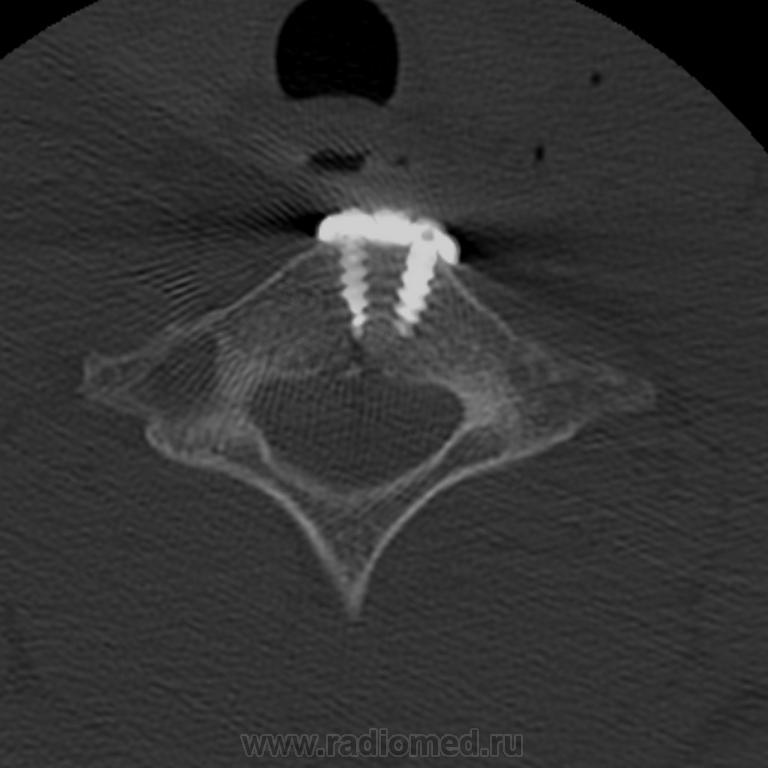

Пол пациента: Мужской пол Тип патологии: Травма Область исследования: Скелетно-мышечная система Методы исследования: КТ Снова молодой ныряльщик... Поставили имплант. Жаль, что это ему не поможет нормально жить. https://radiomed.ru/sites/default/files/styles/case_slider_image/public/user/5374/image00002.jpg?itok=P5NKASeg https://radiomed.ru/sites/default/files/styles/case_slider_image/public/user/5374/image00003.jpg?itok=DxGAT6xz https://radiomed.ru/sites/default/files/styles/case_slider_image/public/user/5374/image00004.jpg?itok=pPUmQRPJ ID:5360 Втр, 10/08/2010 - 23:18 #1 Сергей Нагорный Не на сайте Был на сайте: 9 лет 8 месяцев назад Зарегистрирован: 13.07.2010 - 22:49 Публикации: 1370 Не добавились снимки, еще разок...Приложения: С уважением, С.Н. Нагорный Ср, 11/08/2010 - 16:19 #2 Vikkur Не на сайте Был на сайте: 4 года 7 месяцев назад Зарегистрирован: 24.09.2009 - 14:34 Публикации: 1749 Что тут позвонок "треснул"? или имплант сломался? Виктор.

Что тут позвонок "треснул"? или имплант сломался?